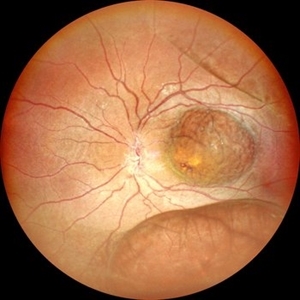

Von Hippel-Lindau Syndrome

Color photo montage of a 19-year-old female with Von-Hippel-Lindau syndrome.

Photographer: Dr. Akansha Sharma-Retina Foundation, Ahmedabad

Condition/keywords: angioma, Von Hippel-Lindau